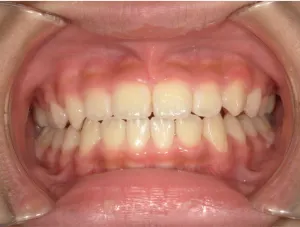

治療後⑧小6(12y3m):モノブロック装置継続中

治療後⑨中2(13y11m):モノブロック装置継続中

咬み合せも安定していて、口元の突出・口唇閉鎖不全も改善

*レントゲンや歯の萌出状況などから成長が終了していると考えられるため、現在残っている隙間や上下正中の不一致を改善するためマルチブラケット法へ移行するか検討中です。

治療は歯並びや口元などの状態から非抜歯治療で行う予定です。